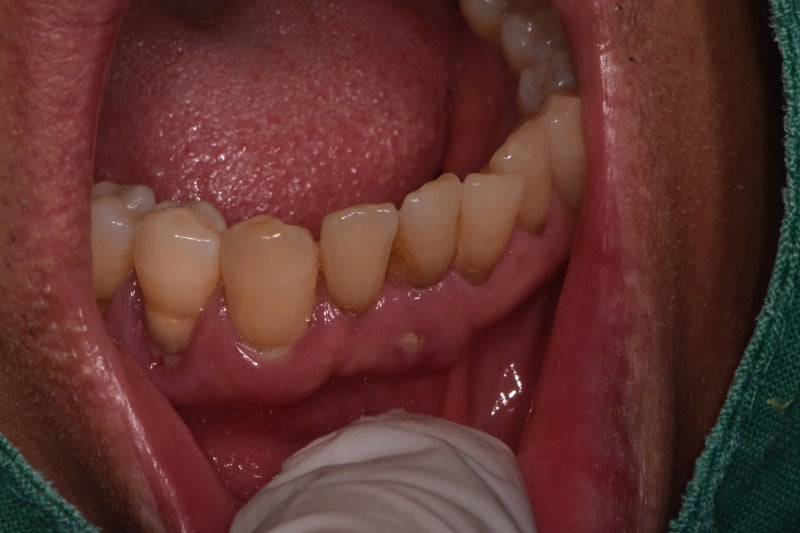

흔들리는 하악전치 크라운

아래 앞니 브릿지, 치주염으로 인해 흔들리는 아래 앞니, 발치시 빠른 치료. 그냥 항상 그러는게 아니라… blog.naver.com 위의것들을 더 많이 하는데 아랫앞니와 아랫앞니가 연결되어 있는 중절치와 측절치 4개가 같은 수명을 가지고 있습니다. ..흔들때 다같이 흔들어주세요-_- 할거면 4빼고 33브릿지 33브릿지 3xxxx3 원래 치과에서 앞니 6개를 아래 송곳니 2개로 교체하는 치료를 많이 하지만 저희는 아직 덜 그리고 상대적으로 안정적인 치료가 하악 전치부에서 흔들리는 일체형 임플란트보다 심미적으로 더 만족스러울 수 있습니다. 뼈이식은 서울덴치과의원 원장으로 꼭 필요한 앞니임플란트와 아래턱앞니임플란트를 자주 시행하고 있습니다. 전치부 임플란트는 하악전치, 하악전치… blog.naver.com 전치 임플란트 재수술 과정에서의 주의사항, 하악전치 임플란트 브릿지 치료 -3 4- 5-6 임플란트 순서… blog.naver .com은 임플란트 2개, 하악중절치/측절치 4개, 하악중절치/측절치, 임플란트 브릿지가 2개인데 4개 다 뽑기가 좀 애매하네요. 하악 측절치와 측절치는 아직 남아있습니다 사용하고 싶을때 사용해보세요 이번에는 2개 빼고 옆으로 가서 2개를 브릿지로 사용해보세요 . 아래 앞니가 앞니에 이물질이 끼인 것처럼 많이 부어있죠? 고름이 낭자 치아를 씻는 잇몸치료는 치주치료의 기본인 치주치료, 잇몸치료는 치료법이 없습니다. 보지 않았다. 평소에도 같은 일을 반복해서 하는 편인데… blog.naver.com 열정이 치료해준다, 아까 농포라고 하지 않았어? 사실 이게 치아세정+치근활택술, 치주치료인데 청소를 해도 치석이 벽에 붙어있어요-_- X-ray 필름에서는 앞니 두개가 많이 흔들리고 많이 움직이지만, 아직은 조금 나은 편이지만 치료계획을 설명한 후 예약비는 서울치과에서 공개한 무보험 진료비, 세라믹모자이크 시술비, 임플란트 가격, 뼈이식비, 지르코니아 크라운 가격입니다. 아무리 멀리 떨어져 있어도 다시 예약을 잡고 병원에 가서 치료를 받아야 합니다. blog.naver.com 위 링크 참조 치아변색, 지르코니아 크라운 가격 60만원이 아닌 90만원, 미용시술이 비싼 이유 잦은 앞니, 신경치료(미백)후 치아변색 및 색상개선 모양개선 . 전치부 성형용 지르코니아 크라운… 전치부 문제가 있는 환자의 타원형 폰틱 브릿지 뼈 이식. 기존에 PFM 크라운과 브릿지 치료를 이미 받은 환자라면 PFM은 어떨까? blog.naver.com 이 치아를 뽑은 후에는 잇몸이 상대적으로 많이 처진 상태라 아직은 너무 맛이 없기 때문에 뼈이식, 잇몸이식, 오벌브릿지 등을 하면 남자라서 많이 추가했고 그냥 기본만 하기로 했다. 치료는 하악 중절치 2개를 발치하고 당일 앞니가 나지 않도록 임시 치아를 삽입하는 것으로 시작되었습니다. 세게 씹을 때 앞니가 서로 닿지 않도록 조정 근관치료 없음, 근관치료가 필요한 즉시 시작, 현재까지는 증상이 없어 그대로 두고 발치 부위가 안정될 때까지 약 6주 대기 인상 준비 치아는 괜찮았습니다. 환자는 첫 번째 임시 치아의 치은 부분이 짧은 것을 우려합니다. 입어보면 이렇게 괜찮아 보여서 아주 만족하시고 금새 지르코니아 크라운으로 갈아입으세요 ㅎㅎ 역시나 남자들과 아저씨들(…)은 세세한 것보다는 자세히 보니까 맘에 드시면 괜찮아요 그것! ! 그 사람이야! ! 정원사 같은 남자! 정원사가 디자인을 확인한 후 지르코니아 크라운이 나왔습니다. 임시 치아와 거의 동일한 디자인의 지르코니아 크라운. 나는 거울을 들여다보았고 -, – (사진을 더 찍을게) 차분한 사진을 하나 더 찍을게. 사실 이전에 키우던 하악전치와 하악전치가 치주염으로 인해 흔들렸습니다. . 그냥 항상 그러는 건 아닌데… blog.naver.com 이 녀석은 처음 왕관을 썼을 때보다 시간이 지나면서 많이 좋아졌습니다.전보다 훨씬 좋아진 지르코니아 하악전치 브릿지 시술 케이스 롬 168 4층 예약